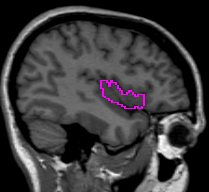

The insular cortex is “hidden” between the temporal and inferior parietal corticies. By drawing sulci lines in the sagittal view, we gain an outline of it in the coronal. Choose a sagittal slice where insula is clearly visible (Fig 1), then draw a “circle” around it (Fig 2). Do this for several slices and for both hemispheres.

Figure 1              Figure

2

Once you have drawn your sulci lines, the insula should be clearly outlined (by little dots) in the coronal view (Fig 3). This is particularly useful in the more anterior slices.

Figure 3